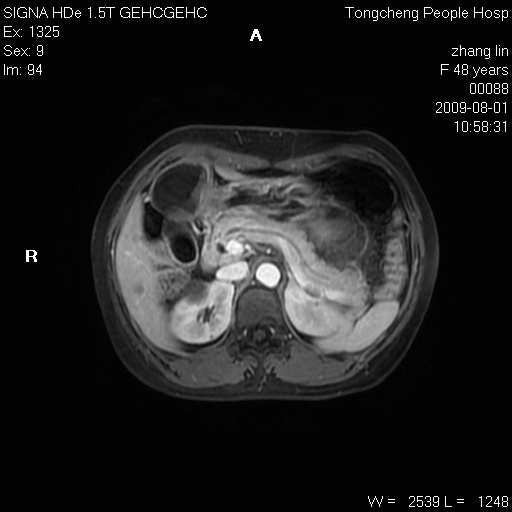

女,48岁。健康体检,彩超发现右肾占位性病变。平素健康。

临床诊断:右肾占位性病变,性质待定(囊肿?肿瘤?)。

上中腹部mr平扫+增强扫描,图像如下:

右肾上极见一类圆形病灶,t1wi呈等信号t2wi呈等高混杂信号,三期增强无强化,边界清---考虑囊肿出血。

同反相位均表现为等信号,病变无强化,考虑含蛋白的囊肿可能,弥散加权相或许有些帮助,

慢性胆囊炎